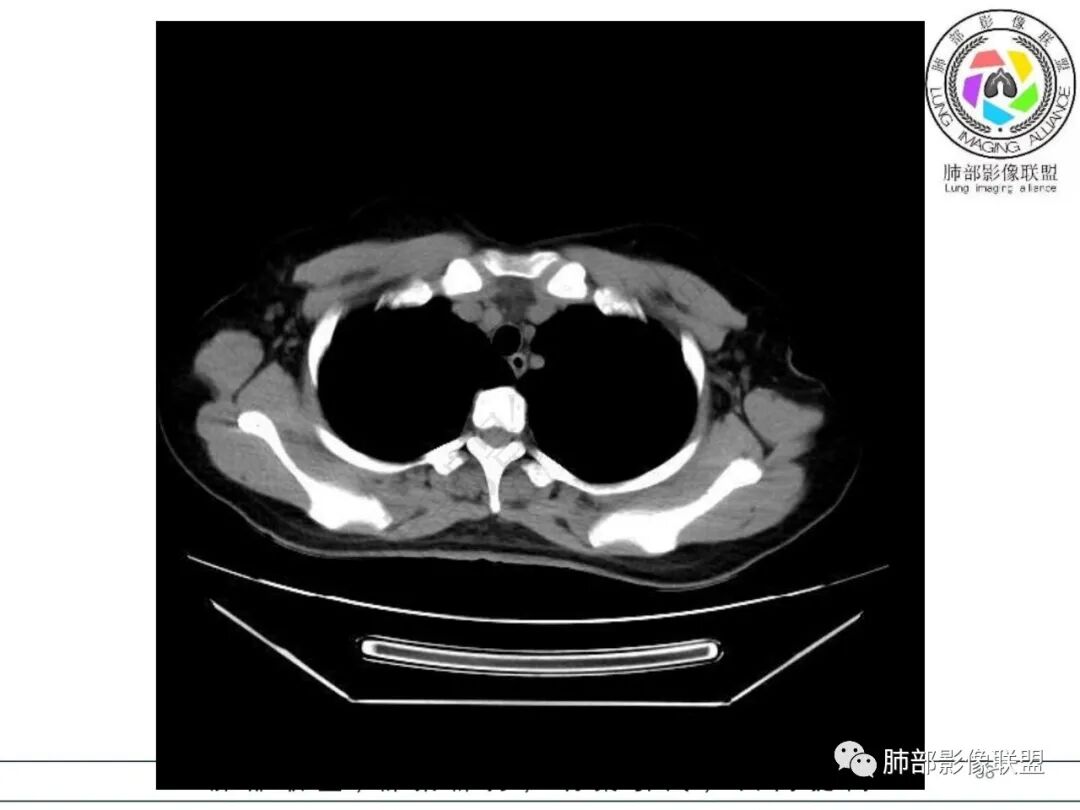

1.临床病史:急性病程,发热畏寒,乏力纳差,恶心呕吐,白细胞不高,CRP及血沉升高。

2.影像特征:右肺下叶局限性实变影伴晕征,边界不清,内部支气管尚通畅,实变区密实区边缘稍膨隆。符合炎性病灶特征。

3.综合分析:急性病程,炎性指标高,常见的是普通社区肺炎,如肺炎链球菌感染等。但本例患者临床表现较重,应先表现相对较轻,白细胞不高,须考虑非典型肺炎的可能性。本例隐球菌荚膜实验阴性,而军团菌临床症状一般较重,影像分布也更广泛、进展迅速,多器官损害更明显。因此考虑鹦鹉热衣原体可能性更大一些。其他如腺病毒等感染也是需要排除的。

最终支气管镜灌洗NGS确诊为鹦鹉热衣原体感染。